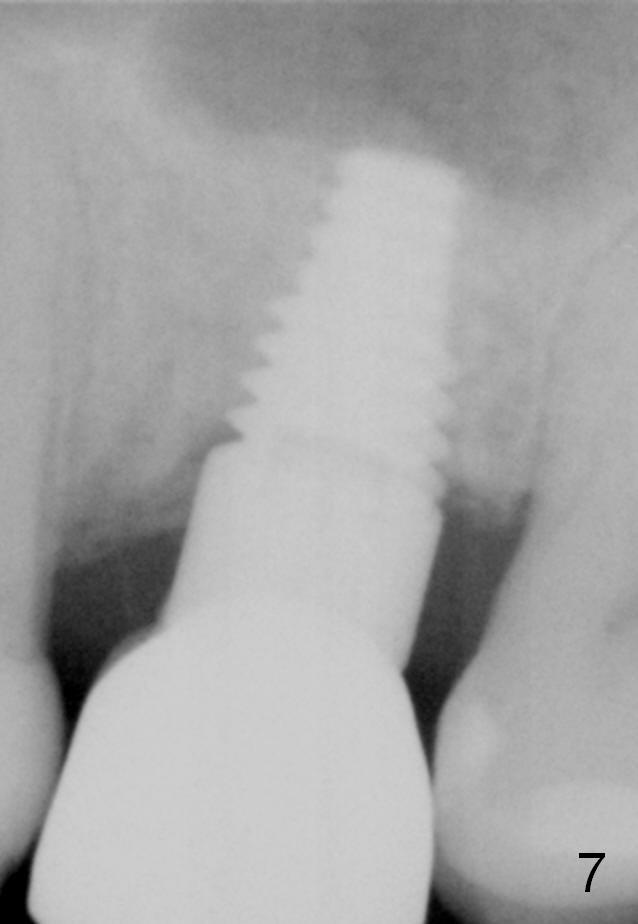

A 48-year-old lady has lost #14 for a while (Fig.1). It looks that bone density at the site of #14 is lower than that mesial to the 2nd premolar. The buccolingual width is wide clinically, although the mesiodistal distance is short (8 mm, Fig.2). A 4-mm tissue punch is used for access. When 1.5 mm pilot drill is used to start osteotomy, it feels that bone density is not low. The first bone expander (2.6 mm) cannot penetrate the bone. Therefore reamers 2.5-3.5 mm are used to increase osteotomy at the depth of 6 mm from the gingival margin. A 4.5x11 mm tap drill is inserted ~ 7 mm with resistance (Fig.3). After 5x11 mm tap, autogenous bone mixed with Osteogen is pushed into the osteotomy and upward. A 5x11 mm implant is placed with > 60 Ncm (Fig.4). After the last X-ray, the implant is torqued 5 more times so that the distal last thread may be able to be fully engaged to the bone. Fig.5 is CT coronal section at the site of #14 5 days postop (B: buccal; L: lingual). Fig.6 is taken 5 months postop with maintenance of sinus lift (*). The crown dislodges 16 months post cementation. In fact the abutment is also loose. The latter is resin bonded, followed by crown cementation (Fig.7). It appears that when the implant is 5 mm or less, the unipost should be permanently cemented in order to prevent crown displacement, particularly for a patient with bruxism and partial edentulism.